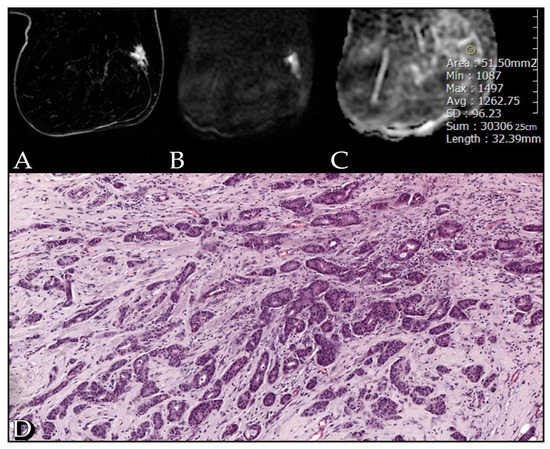

3. Results